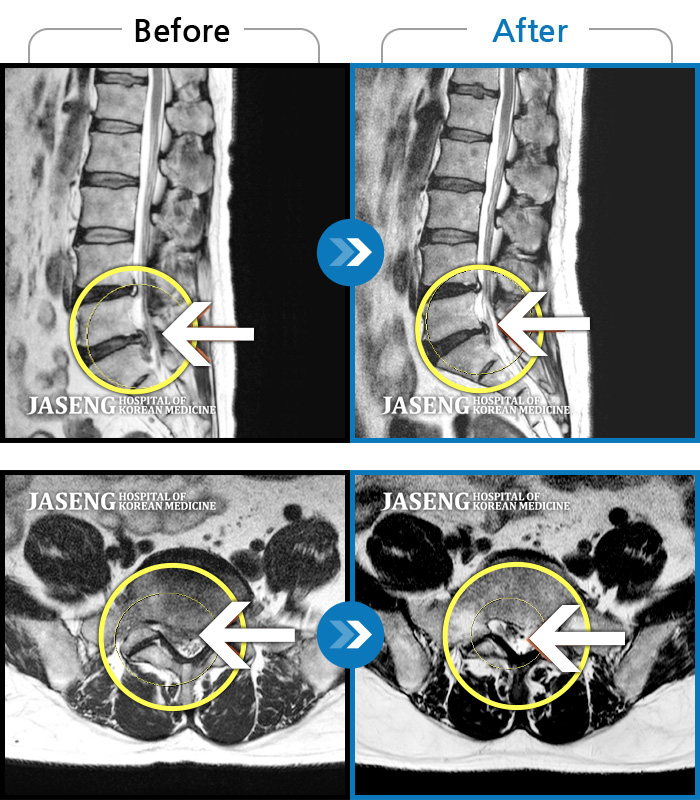

40대 초반 여성 환자인데요,, 처음 선생님 뵈었을 때에 1번,4,5번허리디스크 증상도 증상이지만,

본인 나이에 비해서 10~15년정도 퇴행이 많이 되어있어서 전체적으로 관리가 많이 필요하다고 설명해주셨구요,,

그당시 원장님진료실에서 보았던 저의 엠알아이사진이 아직도 생생히 기억이 납니다 ^^

뼈부분의 색이 왜저렇게 검냐고 여쭈어 보았더니, 말씀주신데로 "퇴행이"많이 되어서 그렇다고 설명해주시면서,,